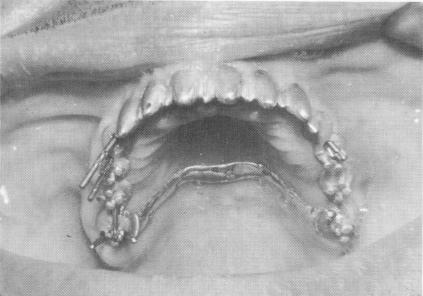

A master stone model with three duplicate implant shafts was prepared (Fig. 10-233), and a scalloped gold template was fabricated from the stone cast. The template included vertical extensions anteriorly, an improvement that eliminates the need for the gold coping connecting bar shown in the previous cases, and mushroom-shaped protrusions in the triplant areas for inclusion in the acrylic cores. These help bind the triplants to the template. Holes were then made between the mushroom-shaped protrusions to accommodate the triplant pins (Fig. 10-234). These holes were determined by taking radio-graphs while the template was in the mouth.

Fig. 10-236. Pin implants were then drilled through the template.